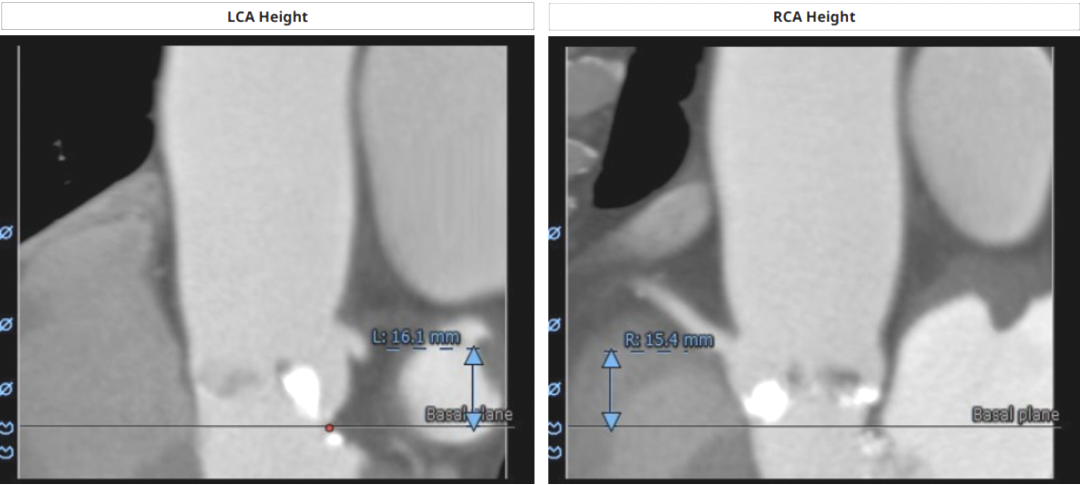

左冠高度:16.1mm,右冠高度15.4mm,双冠高度均可